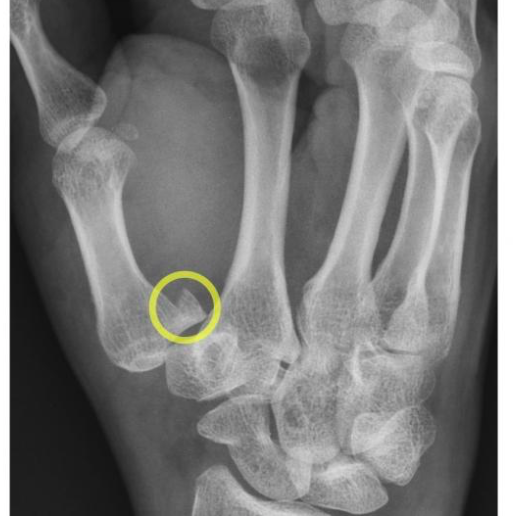

this joint is involved in the Bennet’s fracture